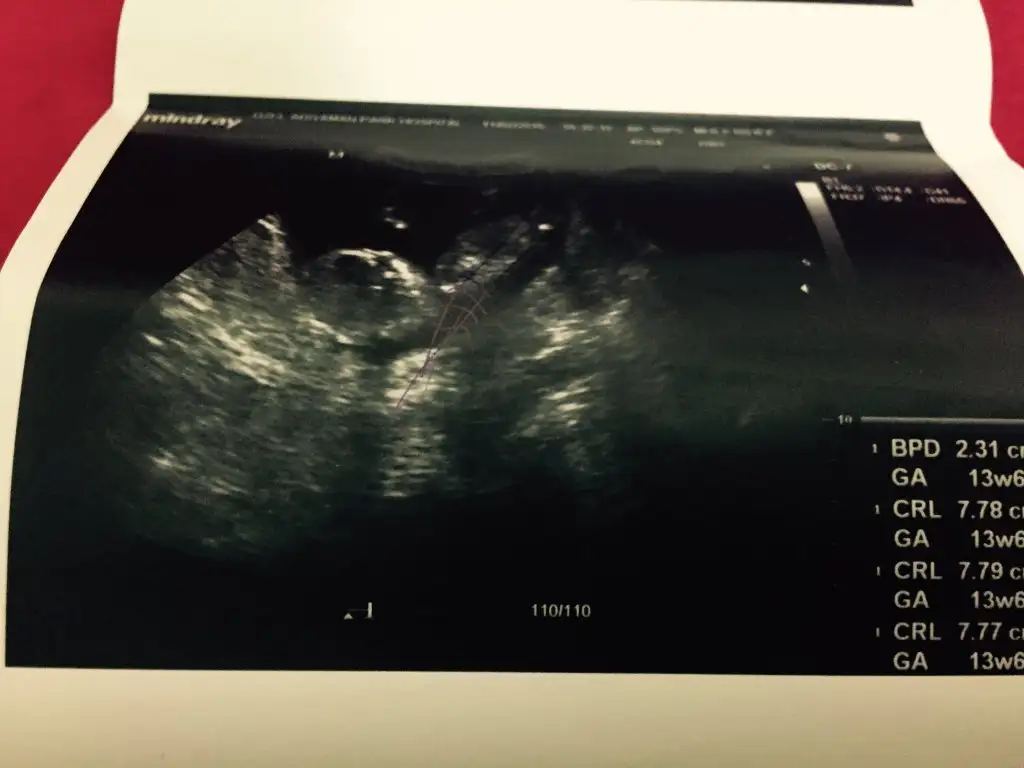

Kizlar bnm bebisimede bakarmisinz rica etsem,doktor 16.haftayibekle dedi,biz 13. Haftadayiz..

o gördüğümüz nub ise açılı sanırım erkekKizlar bnm bebisimede bakarmisinz rica etsem,doktor 16.haftayibekle dedi,biz 13. Haftadayiz..

Cnm bu en son foto 13+6, bunada baksana daha net bu foto..Canım ilk fotografa bakmamıştım bebek tam yan değil hafif arkası dönük sidellanın tahmini doğru sanırım...